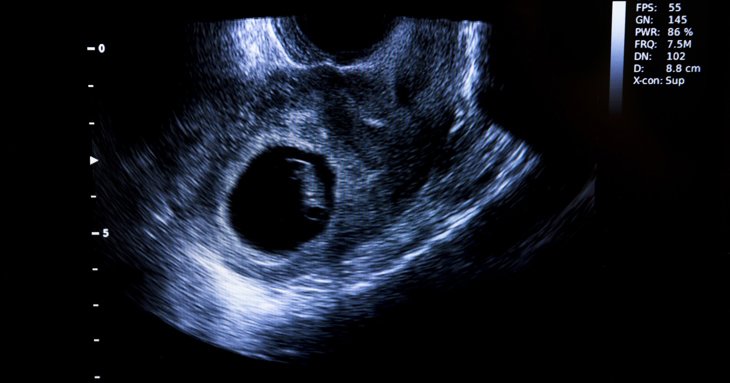

Early pregnancy scans, sometimes called viability scans, can be performed from around six weeks and would usually be to check that all is well with your pregnancy in the early stages. Early pregnancy scans are often performed a bit earlier than 12 weeks, although we would still classify a 12-week scan as an early pregnancy scan. Some people prefer to have a check before 12 weeks, as they feel that it is a long time to wait, but it is a personal choice.

Each stage of pregnancy will have different tasks that can be done at different stages, as the pregnancy changes week by week and what you see at one stage will be quite different from what you would see at another stage.

Early pregnancy scans will tell you if the pregnancy is in the right place, so not

ectopic. They can tell you how many babies you are carrying; let you know how

many weeks into your pregnancy you are, to approximately two or three days either side; and whether or not the

pregnancy is progressing, especially if you have had any issues in the past.

There are specific landmarks that we look for when performing an early

pregnancy scan, such as whether the yolk sac is present. The yolk sac shows

as a small circle on ultrasound and is a food store that is seen before even the

embryo is visible. Early pregnancy scans should also make an assessment of the

pelvic area and ovaries to rule out any unusual pathology.